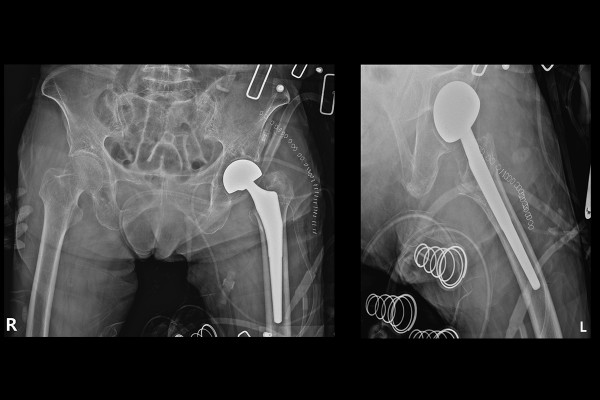

수술은 고관절 인공관절 반치환술(Bipolar hemiarthroplasty hip Lt)로 진행되었으며, 실시간 X-RAY인 C-ARM으로 확인하며 수술을 진행합니다.

수술 후 X-RAY를 보면 좌측 인공관절 반치환술이 잘 된 것을 확인할 수 있습니다.